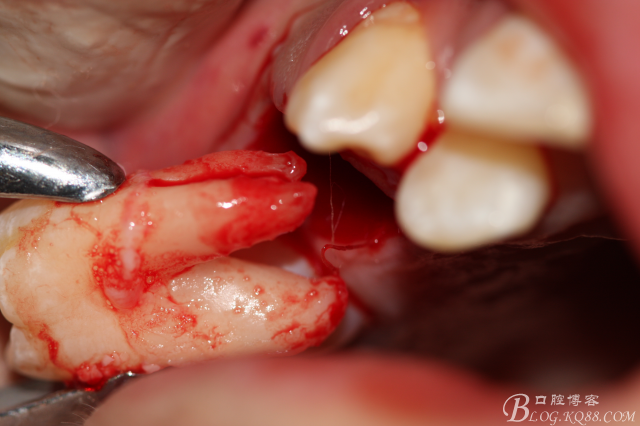

3.術(shù)中拔除上頜第一前磨牙照片